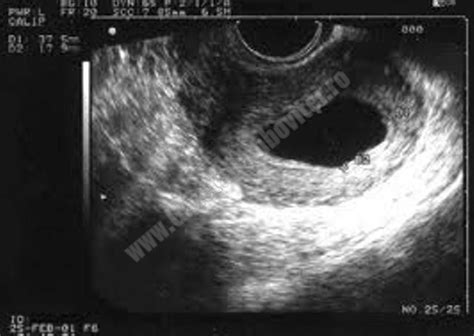

- Ecografia: Aceasta este o investigație foarte importantă și se poate efectua transabdominal sau transvaginal. Pentru un diagnostic precis, se preferă ecografia transvaginală, efectuată cu ajutorul unei sonde speciale. Sarcina anembrionară se diagnostichează în primul trimestru, între săptămânile șapte și nouă, când, în absența unui embrion vizibil, sacul gestațional are un diametru mediu de cel puțin 25 mm.